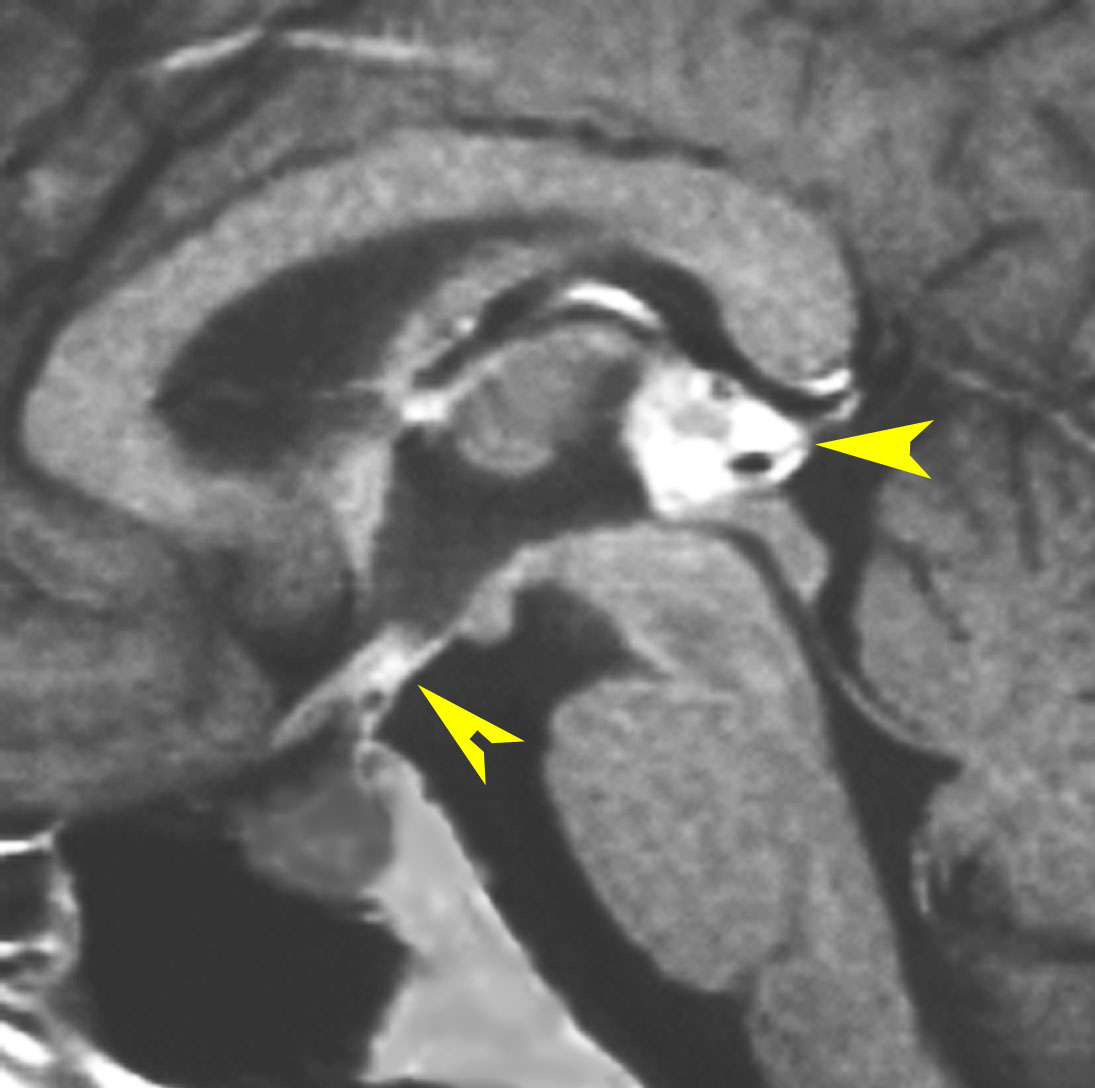

放射線が外れやすい部位は再発源となります

側脳室先端(前角,後角,側頭角,閂),下垂体と大脳基底核に放射線が入らないとその部位から再発します。

再発ジャーミノーマの画像です。延髄背側の閂 ovexという部位に再発しています。

このパターンはとても多いです。なぜかというと,全脳室照射の時に,第4脳室下端のovexの上衣 ependyum を照射野に入れない放射線治療医の先生がいるからです。放射線科の先生にもちょっとした知識が必要なのです。

これは再治療で腫瘍が消えても不可逆的な重症の延髄障害を残してしまいます。